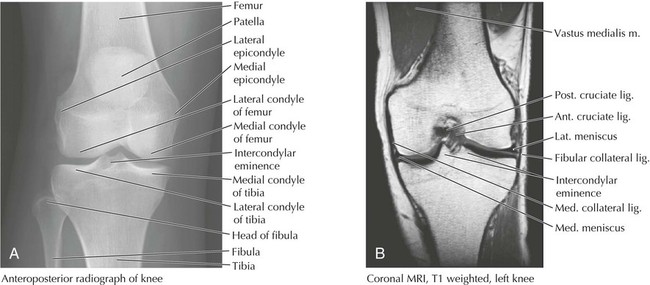

The knee is the most sophisticated joint in the body and the largest of the synovial joints. It participates in flexion, extension, and some gliding and rotation when flexed. With full extension, the femur rotates medially on the tibia, the supporting ligaments tighten, and the knee is locked into position. The knee consists of the articulation between the femur and the tibia (biaxial condylar synovial joint) and between the patella and the femur.

Features of the knee joint are shown in Figures 6-16 (muscle tendon support), 6-17 and 6-19 (ligaments), 6-18 (radiographs), and 6-19 (bursae) and are summarized in Tables 6-12 and 6-13. Because of the number of muscle-tendon units running across the knee joint, several bursae protect the underlying structures from friction (Fig. 6-19). The first four of the bursae listed in Table 6-14 also communicate with the synovial cavity of the knee joint. The vascular supply to the knee primarily arises from genicular branches of the popliteal artery, the inferior continuation of the femoral artery (Fig. 6-13).